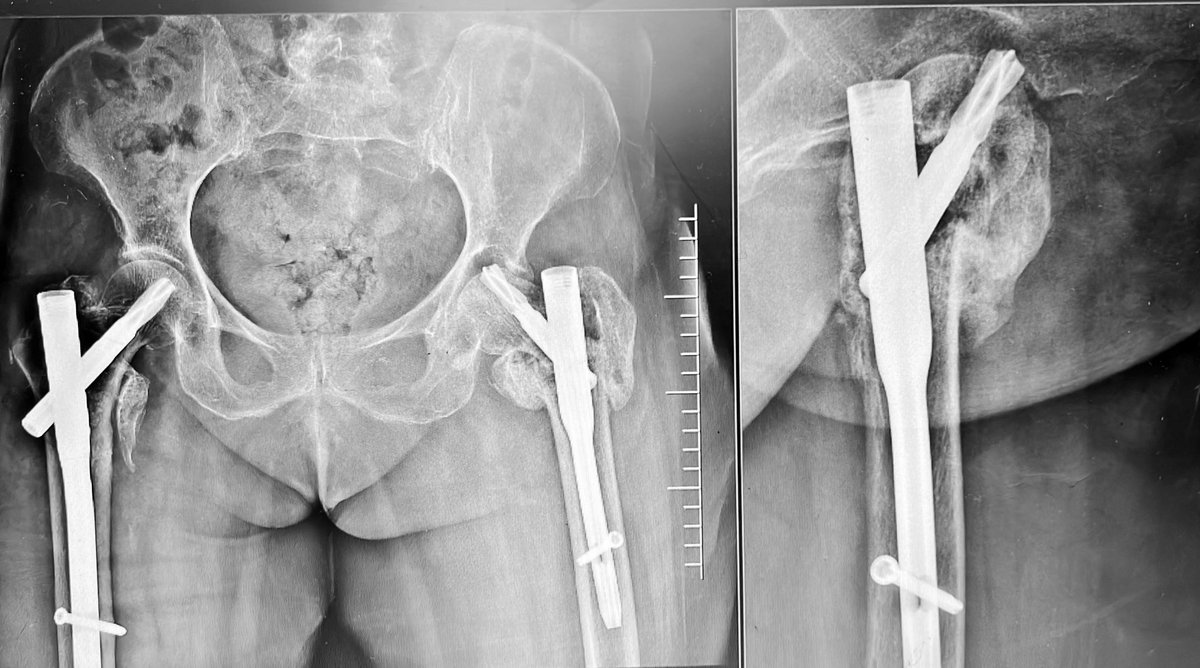

77 yo, pluripathological patient, combo nail and plate. Suprapatellar nail

Dr. Diego López tweet mediaDr. Diego López tweet mediaDr. Diego López tweet media